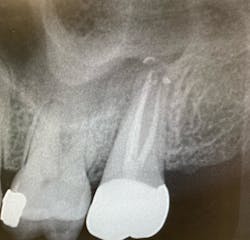

No. 4: Evaluate a cone beam CT scan.

If you can use a CBCT scan, it will give you more detail and can be helpful in discerning the pattern of bone loss, although it won’t necessarily show the root fracture itself. Failure of endodontic treatment commonly occurs at the portal of exit apically (unless there is a lateral canal midroot). Fractures are typically present with lateral bone loss (figure 2).